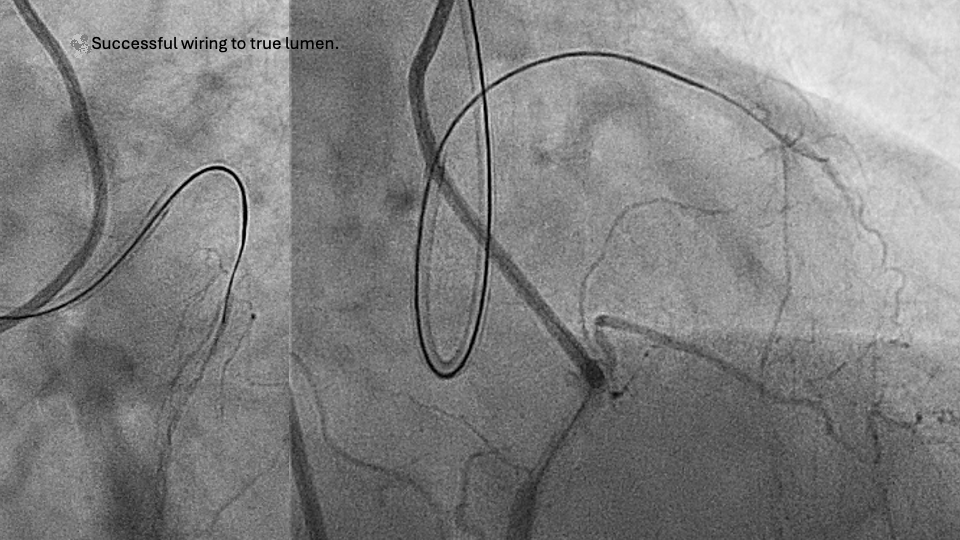

There are 3 parts to AW: (1) proximal cap puncture, (2) CTO body crossing, and (3) distal cap puncture into the distal true lumen. Proximal cap puncture is simple unless complicated by ambiguity or a tough cap, which occurs in 35% of cases.12 The methodology to overcome proximal cap ambiguity and tough proximal cap has been addressed in the CTO algorithms.2-4,7 CTO body crossing can be achieved with wiring and, if necessary, knuckle wiring. However, distal cap puncture remains an unaddressed area in CTO PCI. Although 3D fluoroscopic wiring can be used in distal cap puncture13 and has been shown to be faster, safer, and more successful in retrospective registry data,14 the adoption of 3D wiring has been very limited due to the difficulty in understanding the methodology and forming a 3D mental image. Based on our experience in 3D wiring, we have put together 10 tips and tricks that can be more widely used by all CTO operators to improve their success when performing distal true lumen wiring.